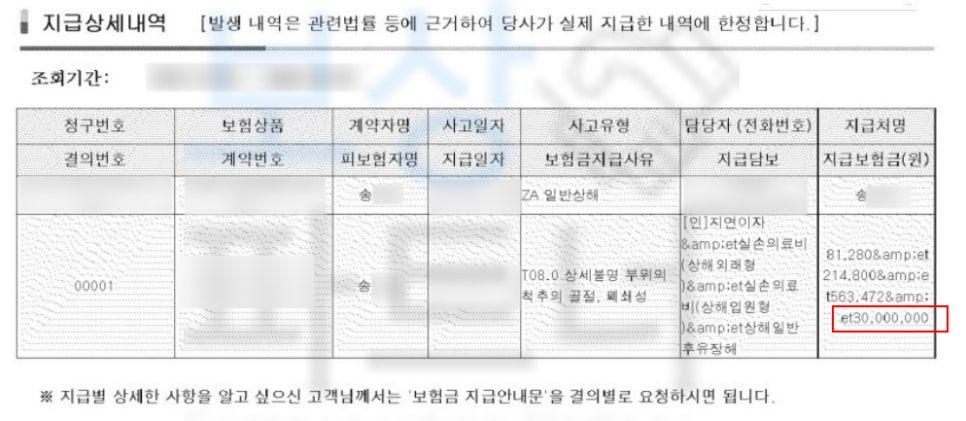

상해일반후유장해보험금 3,000만원

일반상해사망후유장해 보험금 3,000만원,

신주말 일반상해사망후유장해 보험금 1,500만원

재해장해 보험금 900만원

휴일재해 보험금 450만원

가족재해장해 보험금 약 100만원

각 보험사의 재해 및 후유장해 보험금 총 합

약 9,000만원 보상